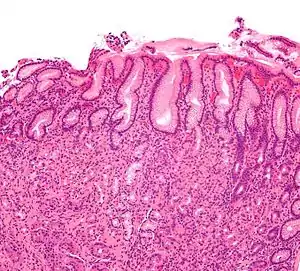

| Micrograph showing gastritis. H&E stain. | |